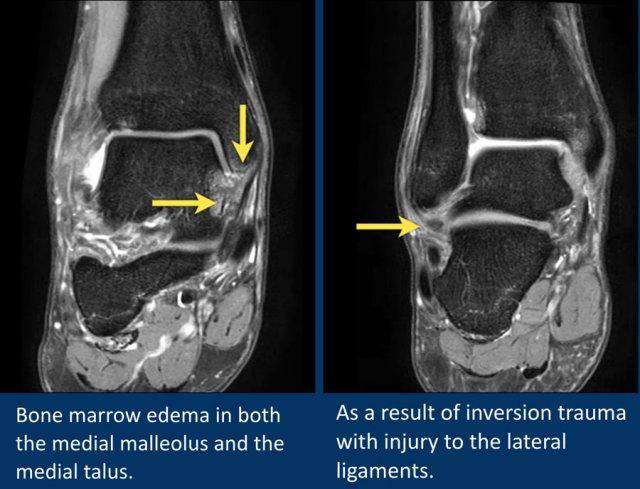

Đây là hai bệnh nhân có phù tủy xương.

Bệnh nhân bên trái có phù tủy xương ở mắt cá trong (malleolus medialis).

Bệnh nhân bên phải có phù nề ở mặt trong xương sên (talus).

Cả hai bệnh nhân đều có chấn thương lật ngoài (eversion injury), gây căng dây chằng delta.

Phù tủy xương ở những bệnh nhân này là do tổn thương bong điểm bám tại các vị trí bám của dây chằng delta.

Bệnh nhân này có phù tủy xương ở cả mắt cá trong lẫn mặt trong xương sên.

Các dây chằng bên ngoài cũng cho thấy hình ảnh phù nề và dày lên.

Phù tủy xương trong trường hợp này nhiều khả năng là do sự va chạm (impaction) giữa xương sên và mắt cá trong thứ phát sau chấn thương lật trong (inversion injury).